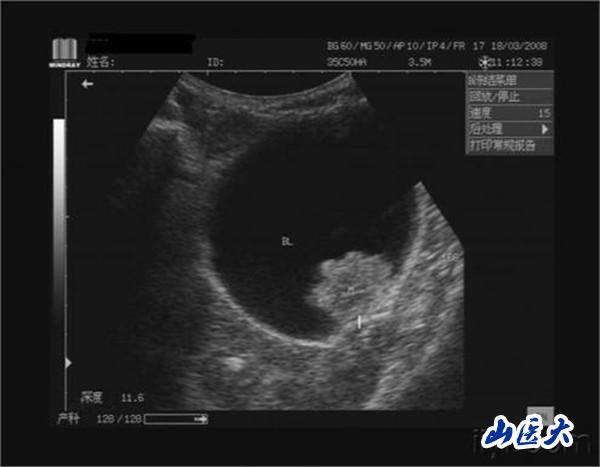

第一医院泌尿外科自2017年引入光纤铥激光以来,利用光纤铥激光高效止血、极浅的穿透深度浅以及无闭孔神经反射的优势完成了上千例经尿道膀胱肿瘤铥激光整块切除术。通过大量临床验证随访、经验总结,完善了该项技术,现已成功开展静脉麻醉下经尿道膀胱肿瘤铥激光整块切除术的日间手术治疗。患者只需在门诊明确诊断,通过麻醉医师的评估后即可进行日间手术。采用监护下麻醉管理的技术真正实现了免插管,术后清醒后即可恢复正常饮食及活动,术后观察2小时便可出院。

膀胱肿瘤是泌尿系统中最常见的肿瘤,多数为移行上皮细胞癌,在膀胱侧壁及后壁最多,其次为三角区和顶部。在国外,膀胱肿瘤的发病率在男性泌尿生殖器肿瘤中仅次于前列腺癌,居第2位,在国内则占首位。男性发病率为女性的3~4倍,年龄以50~70岁为多。非肌层浸润膀胱肿瘤(浅表性膀胱癌)占初发膀胱肿瘤的70%,治疗方法主要是手术切除。

传统的经尿道膀胱肿瘤切除术(TURBT)是应用最广泛的术式,但仍然存在易出血、膀胱穿孔、闭孔神经反射等不足。为避免闭孔神经反射通常需要全麻,导致患者住院时间长、费用高、风险高,而用科学的方法明确诊断和筛选患者,在监护下麻醉的经尿道膀胱肿瘤光纤铥整块切除术的日间手术是安全、有效的,减少了患者住院时间,降低了医疗费用,在保障医疗质量和安全的前提下,缓解了患者“住院难”和“手术难”的问题。